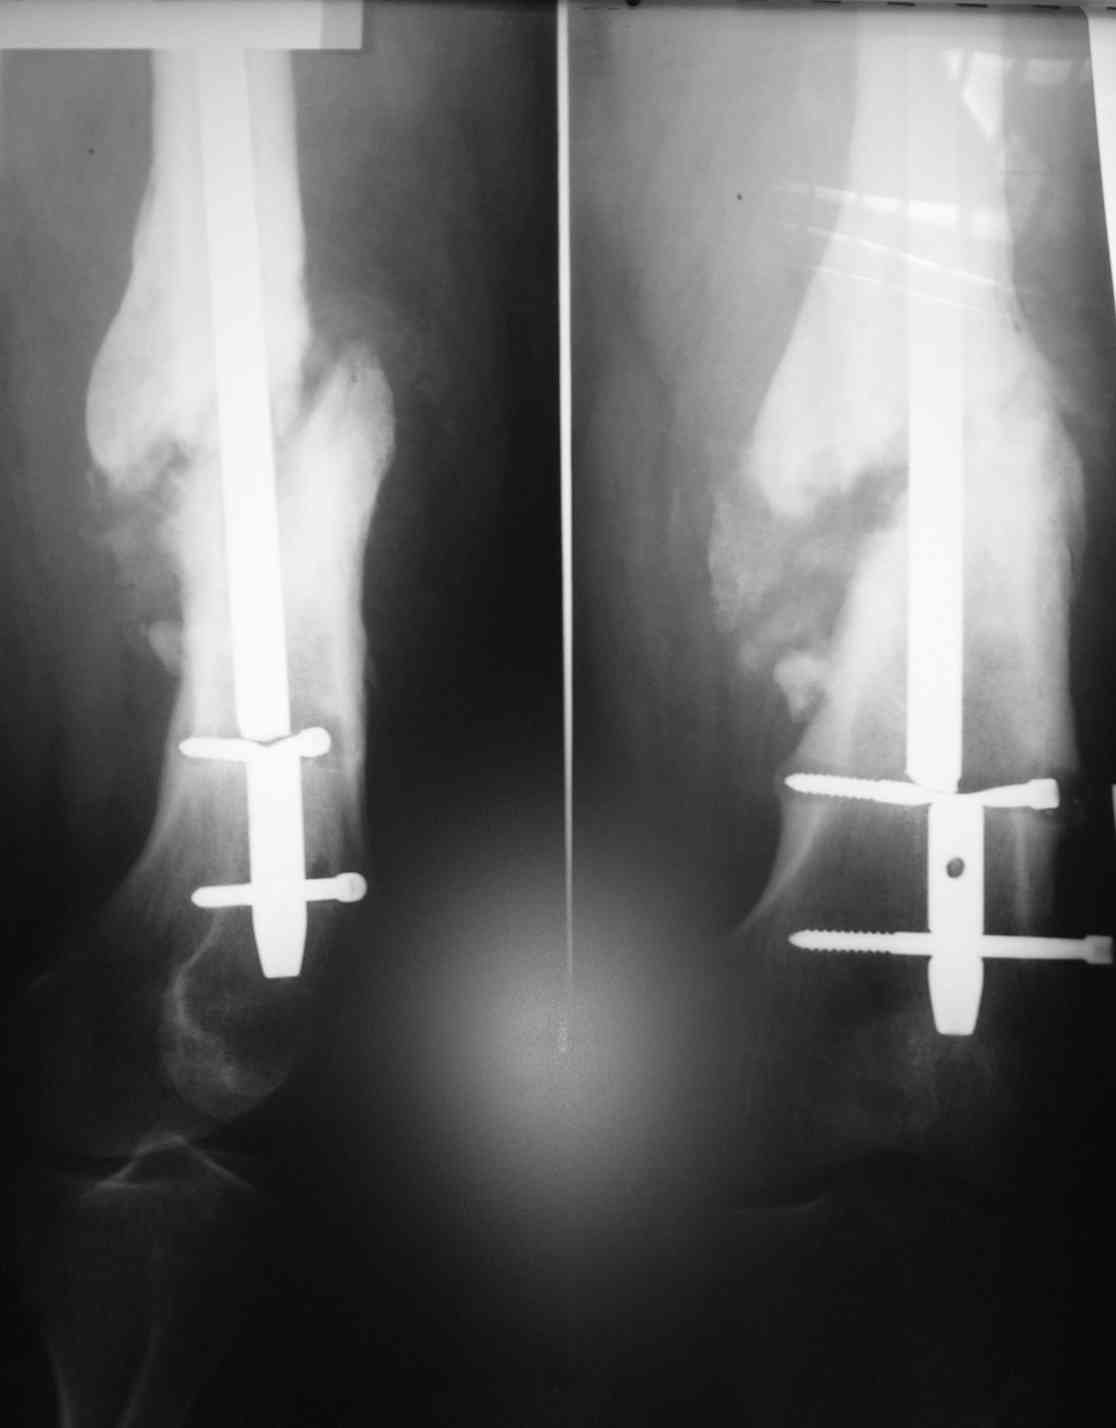

Обратился мужчина, 120 кг, из анамнеза: 1.5 года назад была проведена операция установка

антеграднего стержня в связи с переломом в дистальном отделе бедренной кости. Спустя 1.5

года - несросшийся перелом кости и перелом стержня.

Регулярно травматологом не наблюдался. недавно обратился к травматологу из-за возникшей

боли. Посоветуйте, как наиболее доступно и наименее травматично удалить эту конструкцию?

Тактика дальнейшего оперативноголечения? Мы планируем после удаления старой

конструкции, установку ретроградного бедренного стержня с рассверливанием и первичной

динамизацией.